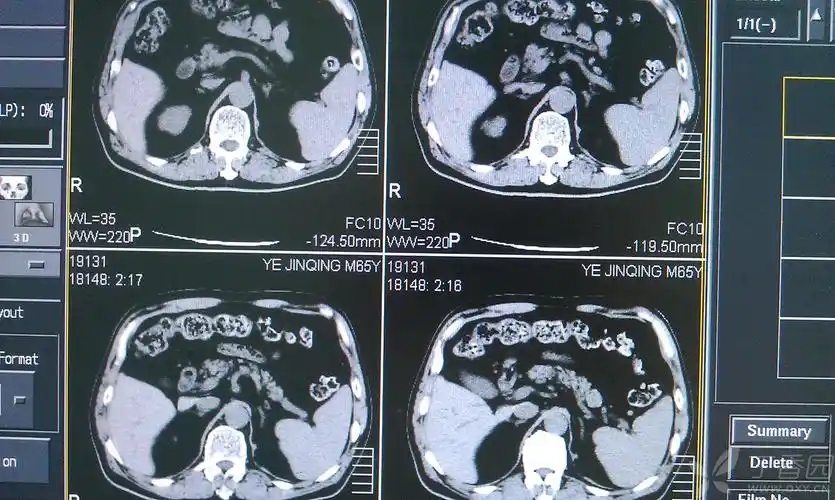

患者右肾怎么了?

结石致重度肾积水 - 好大夫在线

【请教】肾积水?

左肾积水4年

肾积水

ctu示:左肾中-重度积水,左肾盂输尿管移行部梗阻